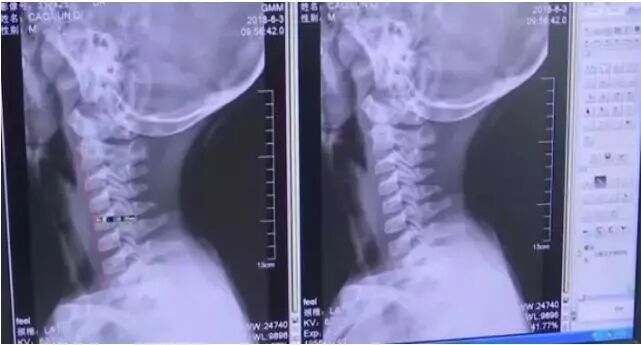

江苏南通一位爸爸带着9岁的儿子到医院就诊。

这位爸爸跟医生反应,近一个月来,儿子经常感到脖子酸胀、有时手指也会发麻。

经过CT检查发现,男孩的颈椎出了问题。

正常的颈椎是带有前曲弧度的,可男孩的颈椎生理曲度消失,竟然变直了!听到这个结果的时候,家长都震惊了。

一般颈椎问题不是都出现在中年和老年人身上吗?孩子才9岁,怎么会出现这种问题?

在医生和家长的沟通下,才知道,原来这名男童一年多来,经常长时间低头玩手机。

长期低头,加上姿势不正确,才给颈椎造成了过重的压力。

医生解释说:低头看手机,颈椎所承受的重量是垂直时的3倍,如果姿势不当,可能让颈椎承受多达27公斤的重量!